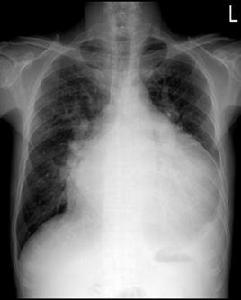

橫膈抬高是指橫膈上升。橫隔是胸、腹腔的間隔。其上是胸腔,其下是腹腔。它位於肺下部胃的上部,呈一拱形的天幕狀,其頂部大約相當於肝臟的上界。簡單點來說橫膈就是分割胸腔和腹腔的肌性組織。呼吸運動都是要靠橫隔的的上下運動來牽拉肺形成呼吸的。複雜點說,膈肌分左右兩葉,由薄層肌腱組織構成,位於胸腹腔之間,呈園頂狀。膈在外側及前、後方與胸壁相交形成肋膈角,在內側與心臟之間形成心膈角。膈的圓頂偏內前方、因而外、後肋膈角深而銳利。吸氣時橫膈位置降低,膈頂相當於第十後肋或第六前肋平面,右膈較左膈約高1~2cm.呼氣時橫膈升高,膈肌運動為呼吸動作的重要組成部分。平靜呼吸時橫膈的運動範圍約為1~3cm,深呼吸可達3~6cm引起橫膈抬高的另一個原因便是,右肺容積減少。

橫膈抬高橫膈抬高多見於胸內或腹內許多病變引起,在小兒原發性肺結核病例中,肺門或氣管旁,尤其是前縱隔淋巴結腫大,可累及膈神經,造成膈神經麻痹或輕度麻痹。膈神經左右各一個,由C4~C6深神經叢發出,從頸部經胸廓上口進入胸腔,在行程中集合一些神經分支,主要來自第6~12肋神經的分支。右側膈神經,在胸廓內位於下腔靜脈右方,末梢分布於右膈肌中央。左肺門前約5.0cm處與心包左側面相連,到達膈肌頂部略在心尖後方,末梢分布在左膈頂的前外側。膈神經麻痹的X線表現為膈頂上升,膈肌活動受限,膈神經輕度麻痹側膈肌抬高不明顯,但透視可見受累側膈肌活動度減弱,讓患者做鼻短促吸氣時表現更為明顯。胸片上單側膈肌升高,同時有肺門淋巴結腫大,可以肯定淋巴結腫大不明顯,這種情況在小兒肺結核中並不少見,往往有兩種情況:一是追溯以前胸片常有腫大淋巴結;其二是不久以後胸片上會出現肺門等處淋巴結腫大。一般規律肺門淋巴結腫大或縮小與膈肌升高和還原是同步的。如果胸片上膈肌升高,雖無肺門明顯增大,往往提示有肺門或氣管旁淋巴結腫大,主要是前縱隔組淋巴結。原發性肺結核引起膈肌升高特點有兩個,一個是兩側肺門區有淋巴結腫大或原發病灶時,膈肌頂抬高的高度相等,經3個月的治療後,左膈頂升高明顯,雙側肺門淋巴結腫大,左肺門表現明顯,經半年治療後左膈肌升高更加明顯,另外肺門淋巴結縮小後,膈肌高度恢復正常。